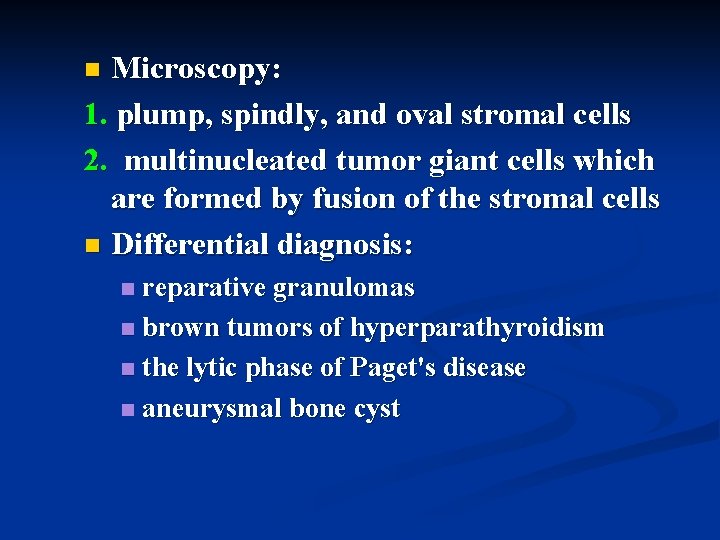

Microscopy: 1. plump, spindly, and oval stromal cells 2. multinucleated tumor giant cells which are formed by fusion of the stromal cells n Differential diagnosis: n reparative granulomas n brown tumors of hyperparathyroidism n the lytic phase of Paget's disease n aneurysmal bone cyst n